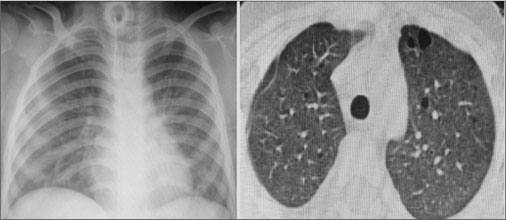

In the PICU, she was intubated and started on mechanical ventilation and supportive care. She developed bilateral pneumothoraces requiring intercostal drainage tubes. Following extubation considering the nonresolution of symptoms and unusual occurrence of pneumothorax in a child with miliary tuberculosis, a chest computed tomography (CT) was performed [Figure 1]. This revealed multiple nodules and thin-walled cysts all over both lungs. Many cysts were subpleural. This characteristic radiological picture suggested LCH. Closed lung biopsy was attempted, but the biopsy findings were noncontributory. The child continued to have respiratory distress and oxygen requirement with bilateral extensive coarse crepitations. She had multiple episodes of worsening of respiratory distress with increased oxygen requirement due to repeated episodes of fresh pneumothoraces on both sides. Besides her respiratory symptoms and signs, she had no other findings to suggest LCH of other organs. Evaluation of blood counts, skeletal survey, and liver function tests was all normal. Considering the typical radiological findings of LCH, the plan was to give her a trial of chemotherapy as per the LCH III protocol (Vinblastine and prednisolone). She was also started on intensive nutritional supplementation. After 2 weeks of therapy, her general condition had not significantly improved and she continued to have episodes of pneumothorax requiring new intercostal draining tubes. In consultation with pulmonary medicine, therapeutic pleurodesis was planned with povidone-iodine. She was given two doses of povidone-iodine on both sides and tolerated the treatment well. After 4 weeks of chemotherapy, her oxygen requirement had reduced and intercostal drain tubes were removed. She tolerated this well with no recurrence of pneumothorax. Her interval assessment at 6 weeks showed a significant improvement in the lung parenchyma but the persistence of few nodules and cysts [Figure 2]. A second 6-week induction course of chemotherapy was administered followed by maintenance chemotherapy for 6 months. She is currently well with no respiratory signs and symptoms with lung imaging showing no nodules or cysts. She has gained weight and has no active disease on follow-up.

| Figure. 1 Serial chest X-rays and chest computed tomography showing bilateral pneumothorax with multiple nodules and cysts on both lungs at diagnosis